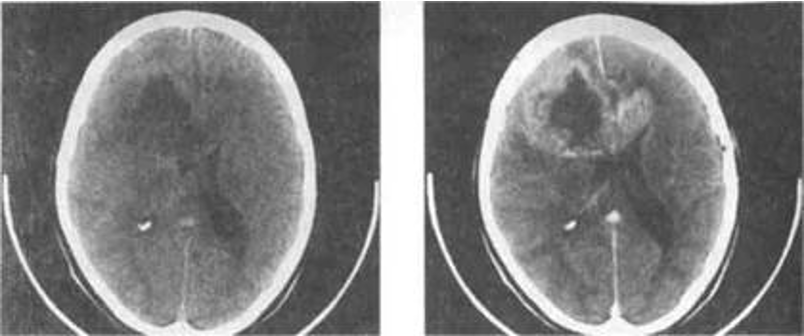

At CT, a glioma typically appears as a solitary, irregular, low attenuation lesion.

Local mass effect can usually be demonstrated. Gliomas ***may calcify, particularly ***

oligodendrogliomas.

Glioma on CT pre and post contrast